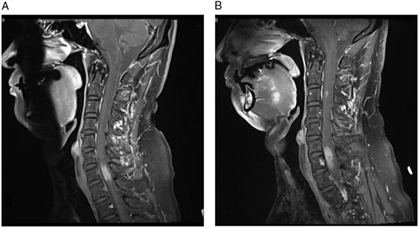

Figure 1: (A–B) T1-weighted post-contrast images demonstrate the progression of cervical spine lesions over time. (A) MRI scan at first admission, demonstrating hyperintense lesion centered at C7. (B) MRI scan 11 months after initial presentation, demonstrating enlargement of the original lesion and a new lesion at C3 level.

Our patient’s MRI of brain, CT of chest, abdomen, and pelvis, and scrotal sonogram were normal at the time of presentation and 18 months later. MR angiography of the neck and intracranial vessels was normal. He did not respond to a trial of steroids, but his symptoms remained fairly stable. Serial MRIs revealed no change until 11 months after presentation at which time a new enhancing nodule (5 mm) appeared at the C3 level, along with slight progression of the original C7 lesion (Figure 1B). Around this time, the patient noted numbness involving his right thorax, but he declined biopsy for a further number of months.